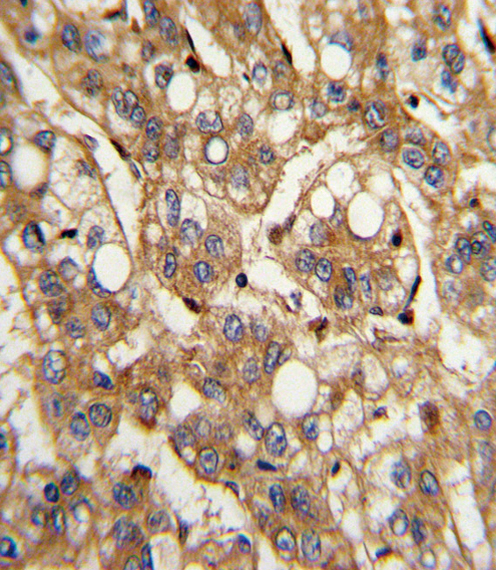

Formalin-fixed and paraffin-embedded human hepatocarcinoma with IFNB1 Antibody (N-term), which was peroxidase-conjugated to the secondary antibody, followed by DAB staining. This data demonstrates the use of this antibody for immunohistochemistry; clinical relevance has not been evaluated. |